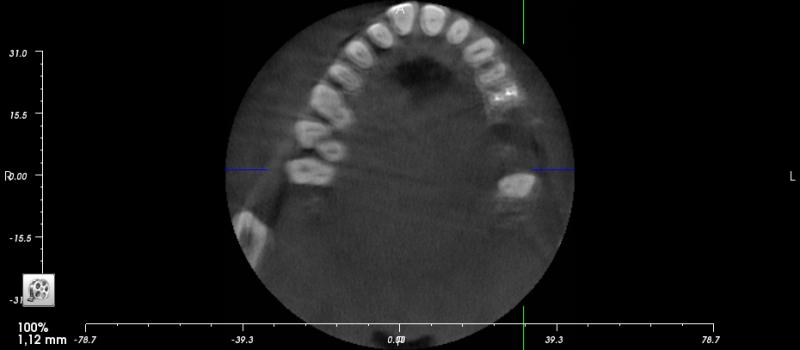

Anderer Kieferchirurg ( 3dim Röntgen) zieht Zahn, stellt fest dass Nebenbackenzahn die Wurzel mit angefräst wurde (Wurzelspitzenresektion erfolgte Juli 2016). Seitdem hat mein Mann immer gesagt im Gaumen steckt was. Zweiter Zahn wird gezogen. Probleme mit Wundheilung. Beschwerden (Schwindel besser) Druck und Schwellungen bleiben.

Erneute kieferchirurgische Untersuchung ( 3DRöntgen) kein Befund oder muskuläre Verspannungen (Sirdalud, keine Hilfe). Cortisonspritze in den Kiefer (Verschlechterung).

HNO und Neurologe schicken zum Kieferchirurgen, diese finden nix auf den Röntgen.

Details kann ich nur geben, wenn ich zumindest ein aktuelles Röntgen habe – hochladen!

Bitte ein aktuelles OPTG hochladen, damit kann man am meisten sagen.

Entschuldigen Sie dass ich mich erst jetzt wieder melde. Es war actionreich hier. Wir haben leider nur einzelne Bilder aus dem 3D Röntgen (08.05.2017, ich hoffe Sie können hier etwas erkennen.

Vielleicht erkennen Sie etwas auf den Aufnahmen.